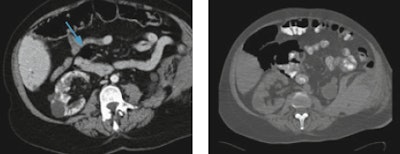

"Bowel injuries, for example, are often missed in CT examinations because in polytrauma patients some specific bowel findings can be misdiagnosed, such as the presence of free small air collections misinterpreted as normal intraluminal air," Basilico noted.

Left: Free air collection (arrow) close to the duodenum, misdiagnosed as normal intraluminal air. Right: One day later, the patient shocked, and a CT performed by means of oral contrast agent and by using bone window setting showed considerable amount of free abdominal air. Images courtesy of Dr. Raffaella Basilico.Radiologists can overcome misdiagnosis by routinely using lung or bone window settings that help differentiate fat from air or multiplanar reconstructions, useful in vascular injuries and skeletal lesions. Moreover, a specific CT protocol for trauma patients, including unenhanced and multiphasic contrast-enhanced CT and, when necessary, a CT cystogram, will help radiologists detect an intra- and extraperitoneal bladder rupture in a case of multiple pelvic fractures, for example.